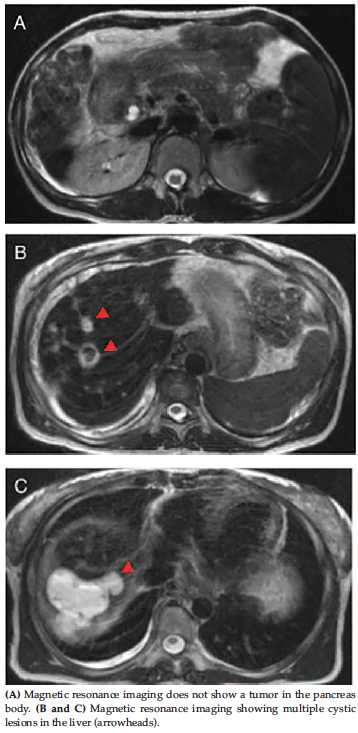

Enhanced computed tomography showed a solitary tumor, 1 cm in diameter, in the pancreatic body. Computed tomography arterioportography showed multiple nodules in the liver. She underwent arterial stimulation venous sampling at the confluence of the hepatic veins and was diagnosed with an insulinoma that metastasized to the liver.

Pathological findings of liver biopsy revealed drug-induced cholangitis and periductal fibrosis 1 year after the SMANCS-TAE. Three years after the embolization, she developed liver failure. Contrast-enhanced computed tomography showed portal vein thrombosis, liver necrosis, and abscess formation in addition to development of a pancreatic insulinoma (Figure 1).

The resected pancreas included a tumor 7.0 × 9.0 mm at the pancreatic body, as shown in the pretransplant enhanced computed tomography (Figure 1). The tumor was pathologically diagnosed as a neuroendocrine tumor and stained positive for insulin and chromogranin A. Histological features were compatible with an insulinoma (Figure 3). No metastatic lesions were seen in the peripancreatic tissue, lymph nodes, or splenic hilar lymph nodes. The mitotic rate was less than 2 per 10 high-power fields, and the Ki-67 index of the tumor was less than 2%. Therefore, the histological grade was G1 according to the World Health Organization 2017 neuroendocrine tumor grading system.14

Figure 1. Abdominal Enhanced Computed Tomography Findings